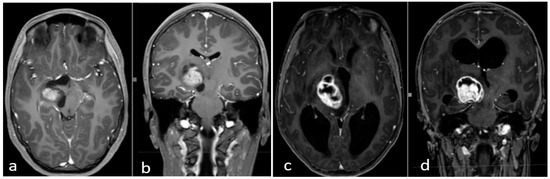

Figure 3.

(a–d) Early postoperative brain MRI with gadolinium. (a,b) An early postoperative brain MRI, T1-weigthed with gadolinium in the axial (to the left) and coronal plane (to the right), for Case A in Figure 2. (c,d) An early post operative MRI, T1-weigthed with gadolinium, for Case B in Figure 1. In detail: In accordance with the nTMS data, we performed a transsylvian approach for Case A (a,b) obtaining a gross total resection (GTR). In Case B (b–d), we performed a trans-temporal approach, obtaining a subtotal resection (STR).

Thalamopeduncular tumors are lesions that arise at the junction between the thalamus and the cerebral peduncles [1] (Figure 4). Most of these tumors are slow-growing pilocytic astrocytoma and displaced the corticospinal bundle, leading to the typical contralateral progressive spastic hemiparesis described as “childhood thalamopeduncular syndrome” [11].

Figure 4.

Preoperative brain MRI of the thalamopeduncular tumor of Case A (a,b) and of Case B (c,d). (a,b) Brain MRI, T1-weighted with gadolinium, showing solid-cystic right thalamopeduncular tumors in the axial plane (on the left) and coronal plane (on the right) in Case A. (c,d) Brain MRI, T1-weighted with gadolinium, showing a right thalamopeduncular lesion with disomogenous contrast enhancement in the axial (on the left) and coronal (on the right) plane in Case B.